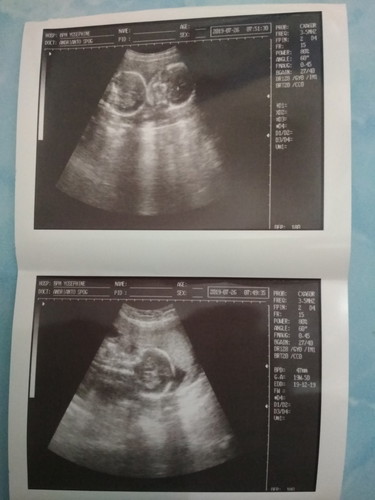

Bunda kmrin pertama kali sya melakukan usg pd usia kehamilan 19w,,meliht hasil ny bayi sya tangan nya gerak2 seneng bnget rasa nya.,dan rasa senang itu bertambah setelah melihat jelas dan keterangan dokter bahwa calon bayi ku kembar,,smpai pulang pun ak dan suami ku msh senyum2 sendiri,smga clon bayi ku sehat2 smua begitupun dg bunda nya Aamiin